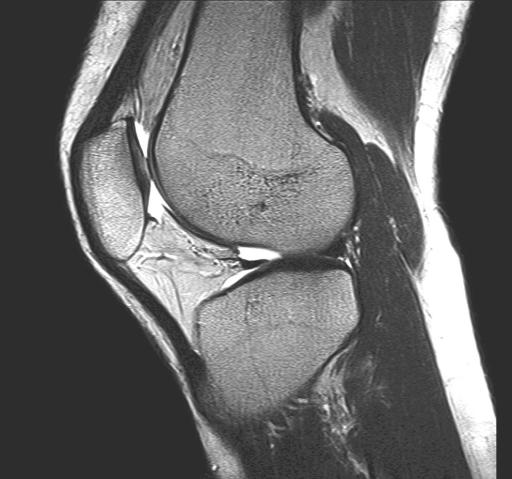

Wegen ihrer hochauflösenden Darstellung von Muskeln, Sehnen, Bändern, Knochen und Knorpel ist die MRT aus der modernen Diagnostik von Erkrankungen des Bewegungsapparates nicht mehr wegzudenken.

Sehnen- und Muskelfaserrisse, Sehnen- und Schleimbeutelentzündungen, Knorpelschäden an den Gelenken, Knochenbrüche, Verschleißerkrankungen und jegliche Entzündungen und Tumoren des Stütz- und Bewegungsapparates lassen sich vorzugsweise mit der MRT abbilden.